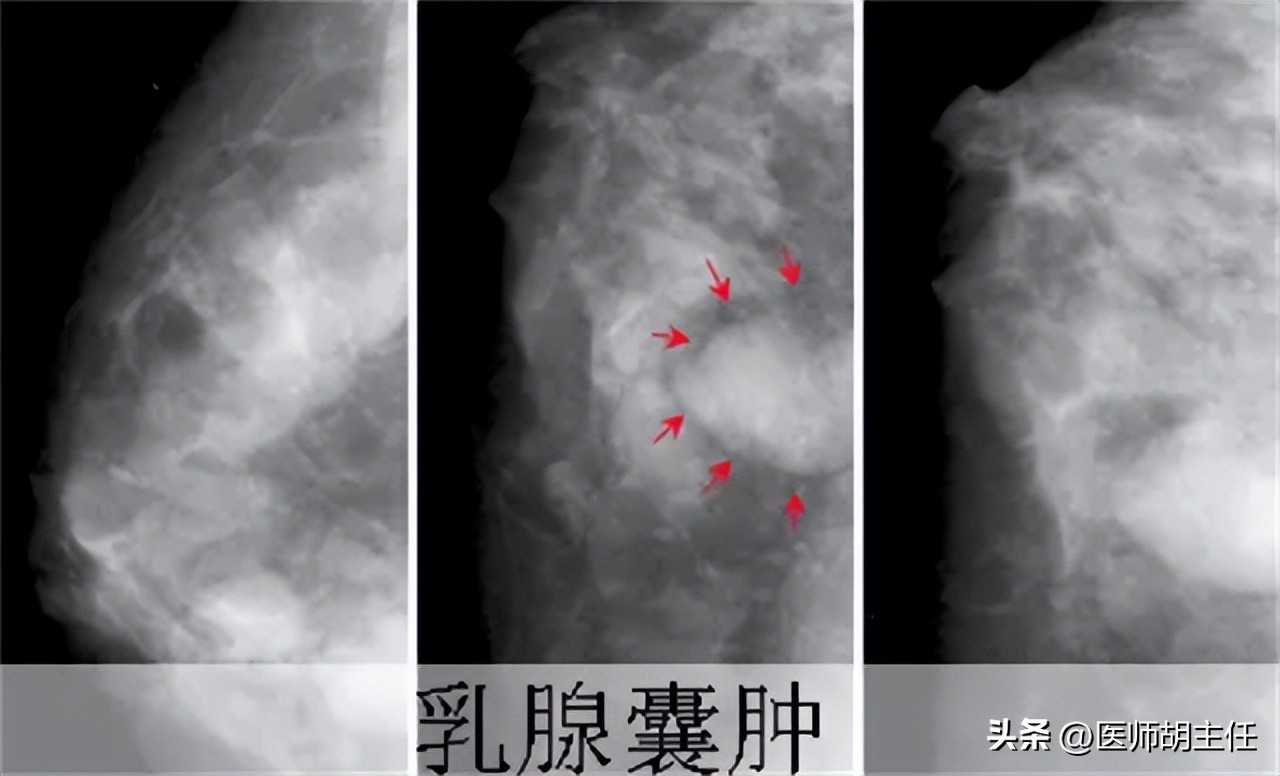

近年来,女性的乳腺疾病诊出率逐年上升,而且也有向年轻化发展的趋势。乳腺囊肿便是其中的一种。

乳腺囊肿分为单纯性乳腺囊肿和积乳性乳腺囊肿。两类囊肿大部分都是良性病变。

大部分单纯性乳腺囊肿都是良性病变,只需要定期进行B超检查,看囊肿是否变大。

但是对于少数可能发生恶变的乳腺囊肿我们也不能掉以轻心,当我们进行B超检查,发现囊肿一直在增大,或者通过病理检查,发现是恶性病变时,无论囊肿大小,都要进行手术切除,避免更严重的后果。